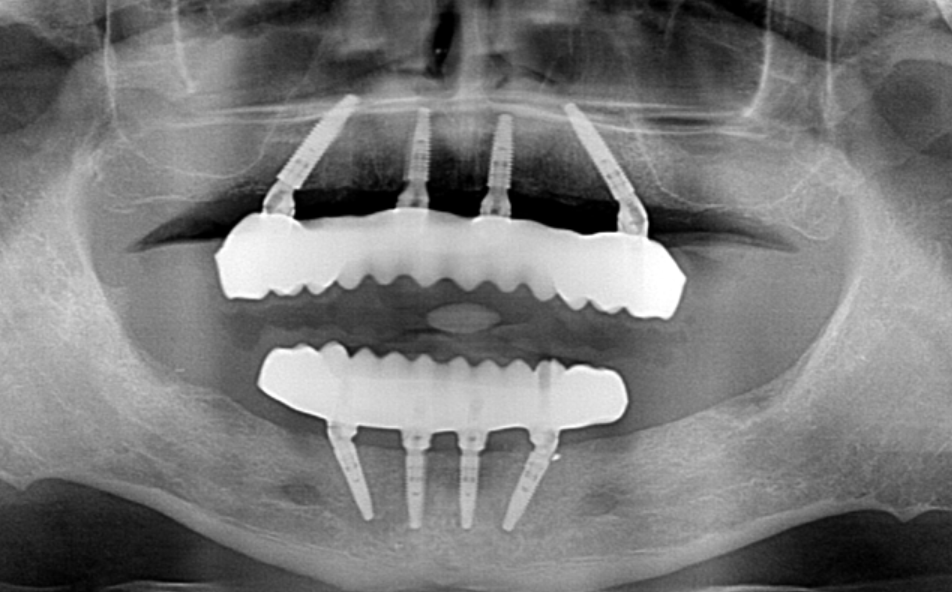

With full mouth dental implants, all the teeth in the patient’s upper and/or lower jaw are replaced with typically four or more dental implants. The specific number of dental implants the patient will need will depend on the condition of their jawbone and what the doctor thinks they will need.

The full mouth implant procedure process begins with an evaluation of the patient’s oral structures and dental history, so they get the personalized new smile they need and deserve. Once the patient’s full mouth dental implant procedure is planned out, the determined number of dental implant posts can be surgically placed in their jawbone.

Most patients will be able to get a temporary prosthesis placed, right after their full mouth dental implant surgery, giving them a new smile in one day. Once their mouth has fully healed, and the customized final prosthesis is made, this final prosthesis can be attached to the dental implant’s so patients get the improved new smile they need.